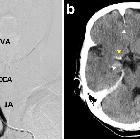

Pulmonary

vein thrombosis and cerebral infarction after video-assisted thoracic surgery of the left upper lobe: a case series. Thrombosis of the right internal carotid artery (ICA) in case 2. a Angiogram of the right cerebral circulation showing occlusion of the right ICA (arrow). b Head computed tomography after thrombectomy revealing cleared ischemic lesion (white arrowheads) and a thrombus at the right middle cerebral artery (yellow arrowhead). IA, innominate artery; SA, subclavian artery; CCA, common carotid artery; VA, vertebral artery; ICA, internal carotid artery; ECA, external carotid artery